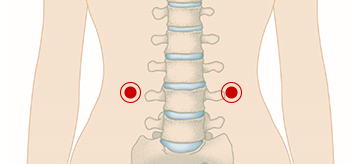

허리가 아플 때 신수혈 지압

신수혈을 지압하면 허리 주변의 기혈을 소통하게 해주어

허리 근육과 인대를 이완해주고 피로를 회복하는 데 도움이 됩니다.

위치 : 허리 부위의 배꼽 높이에서 양쪽으로 손가락 두 마디 정도 떨어진 지점